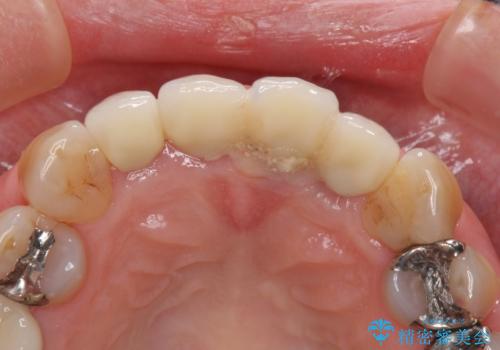

1. 折れてしまった前歯 インプラントによる補綴治療の治療前

1.